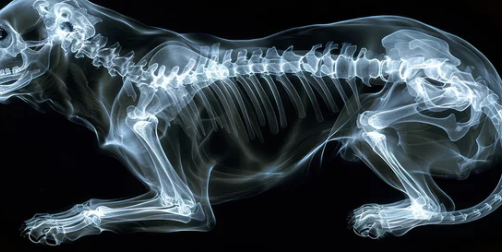

슬개골 탈구는 강아지의 무릎뼈가 제자리를 벗어나는 질환이에요.

수술은 슬개골을 제자리로 고정하고 관절 구조를 안정화하는 것이 목표예요.